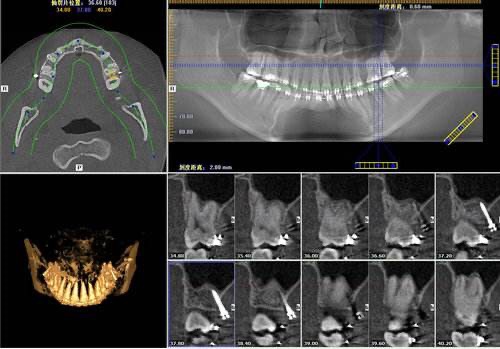

隨著生活水平的提高,人們對(duì)牙科病,牙齒矯形等越來(lái)越重視,口腔曲面斷層攝影在臨床診療中的應(yīng)用越來(lái)越廣泛。為滿足患者及臨床需求,為臨床提供更精確的診斷信息,我院購(gòu)買了KaVo的ORTHOPANTOMOGRAPH OP 3D Pro口腔錐形束計(jì)算機(jī)斷層掃描設(shè)備(CBCT),已安裝調(diào)試投入臨床使用。

OP 3D™Pro高清數(shù)字化口腔影像系統(tǒng)

CBCT片